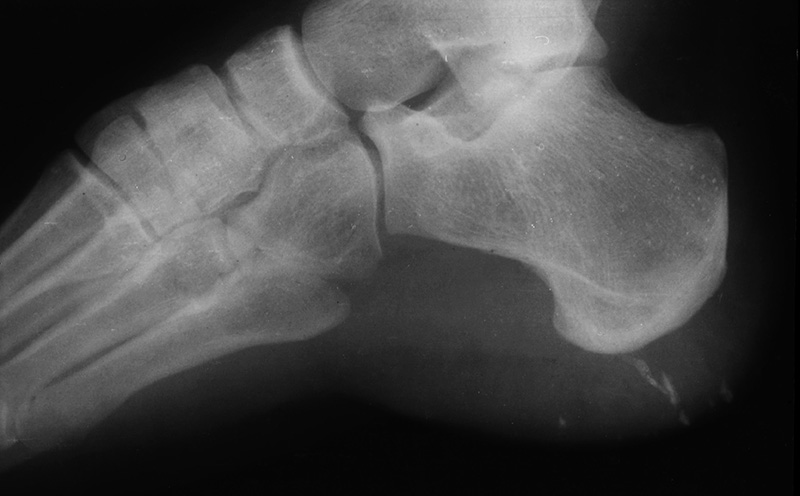

49 year-old man scheduled for knee MRI. History of BB injury to left eye. Frontal and lateral facial views confirm presence of BB in left orbit, possibly in left globe. MRI was contraindicated. 22 year-old man with large piece of wood (arrows) in his calf after being assaulted with a wooden stake. From Hunter, 2003. Permission granted for use of images in this article by Radiological Society of North America (RSNA) 17 year-old boy with barnacle fragments in his heel. He had been water skiing when he came into the dock and unexpectedly encountered barnacles, pieces of which lodged into his heel. (Courtesy George Barnes, MD). From Hunter, 1994